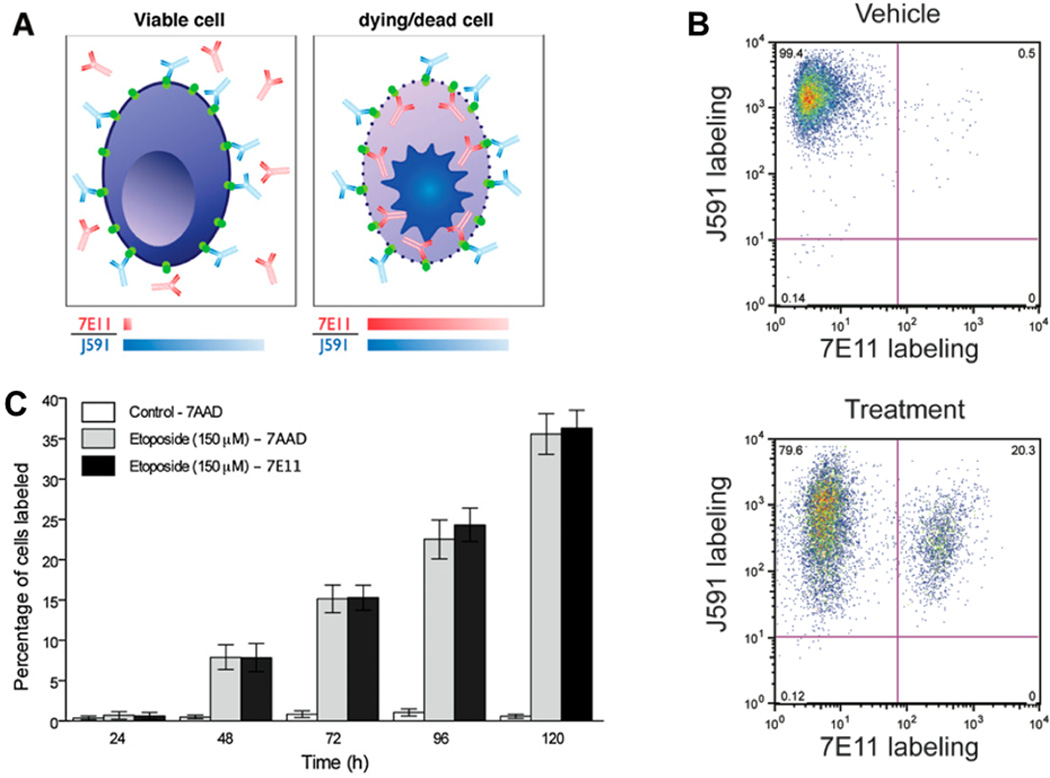

In contrast to 7E11, the humanized J591 monoclonal antibody targets the extracellular epitope of PSMA [26], which is available on live and dead cells alike. J591 is therefore not significantly influenced by changes in membrane permeability. It has been radiolabeled with 89Zr for immunoPET imaging where it has demonstrated high tumor-to-background tissue ratios [23] (Figure 4). Overall, the novel radiotracers 89Zr-7E11 and -J591 represent promising candidates for translation to the clinic for noninvasively diagnosing prostate cancer and assessing its response to treatment. A clinical trial using J591 is currently underway (NCT01543659) as are several trials using J591 as a therapeutic agent. The radiolabeled J591 has also been used to perform targeted Cerenkov imaging in mouse models [3]. Compared to standard optical imaging approaches, Cerenkov imaging approaches using approved radiotracers offer the possibility of relatively rapid clinical translation [27]. Cerenkov radiation is produced when charged particles travel faster than the speed of light through a dielectric medium [27]. Cerenkov imaging exploits the light emission from commonly used diagnostic (e.g. all PET isotopes) and many therapeutic radionuclides [27]. This modality detects a lower amount of light compared to other optical imaging techniques such as fluorescence and bioluminescence, however it benefits from high signal to noise ratios resulting from lack of incident light sources [27].

Figure 4.

Temporal immunoPET images of 89Zr-DFO-J591 (10.9–11.3 MBq [295–305 mCi], 60–62 mg of mAb, in 200 mL of sterile saline) recorded in LNCaP tumor–bearing (PSMA-positive, left shoulder) (A) and PC-3 tumor– bearing (PSMA-negative, right shoulder) (B) mice between 3 and 144 h after injection. Transverse and coronal planar images intersect center of tumors, and mean tumor-to-muscle ratios derived from volume-of-interest analysis of immunoPET images are given. Upper thresholds of immunoPET have been adjusted for visual clarity, as indicated by scale bars. With permission from Holland J et al. (2012) J Nucl Med 51(8):1293-1300